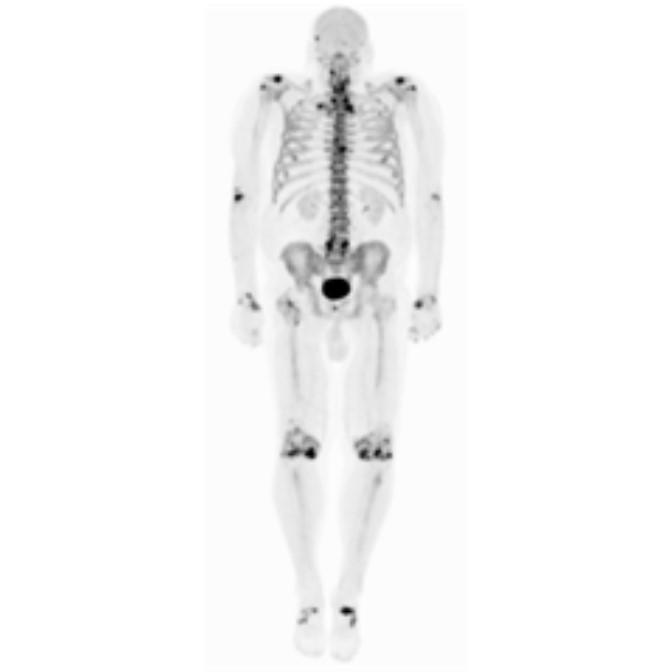

Partial nml and melanoma PET scan